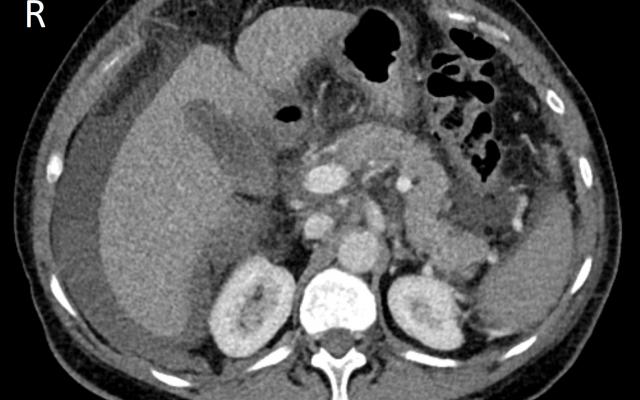

Casus

We beschrijven 2 casussen van vrouwen met overgangsklachten die kort na het gebruik van een voedingssupplement met plantextracten leverfalen ontwikkelden. Dientengevolge ondergingen beide patiëntes een levertransplantatie.